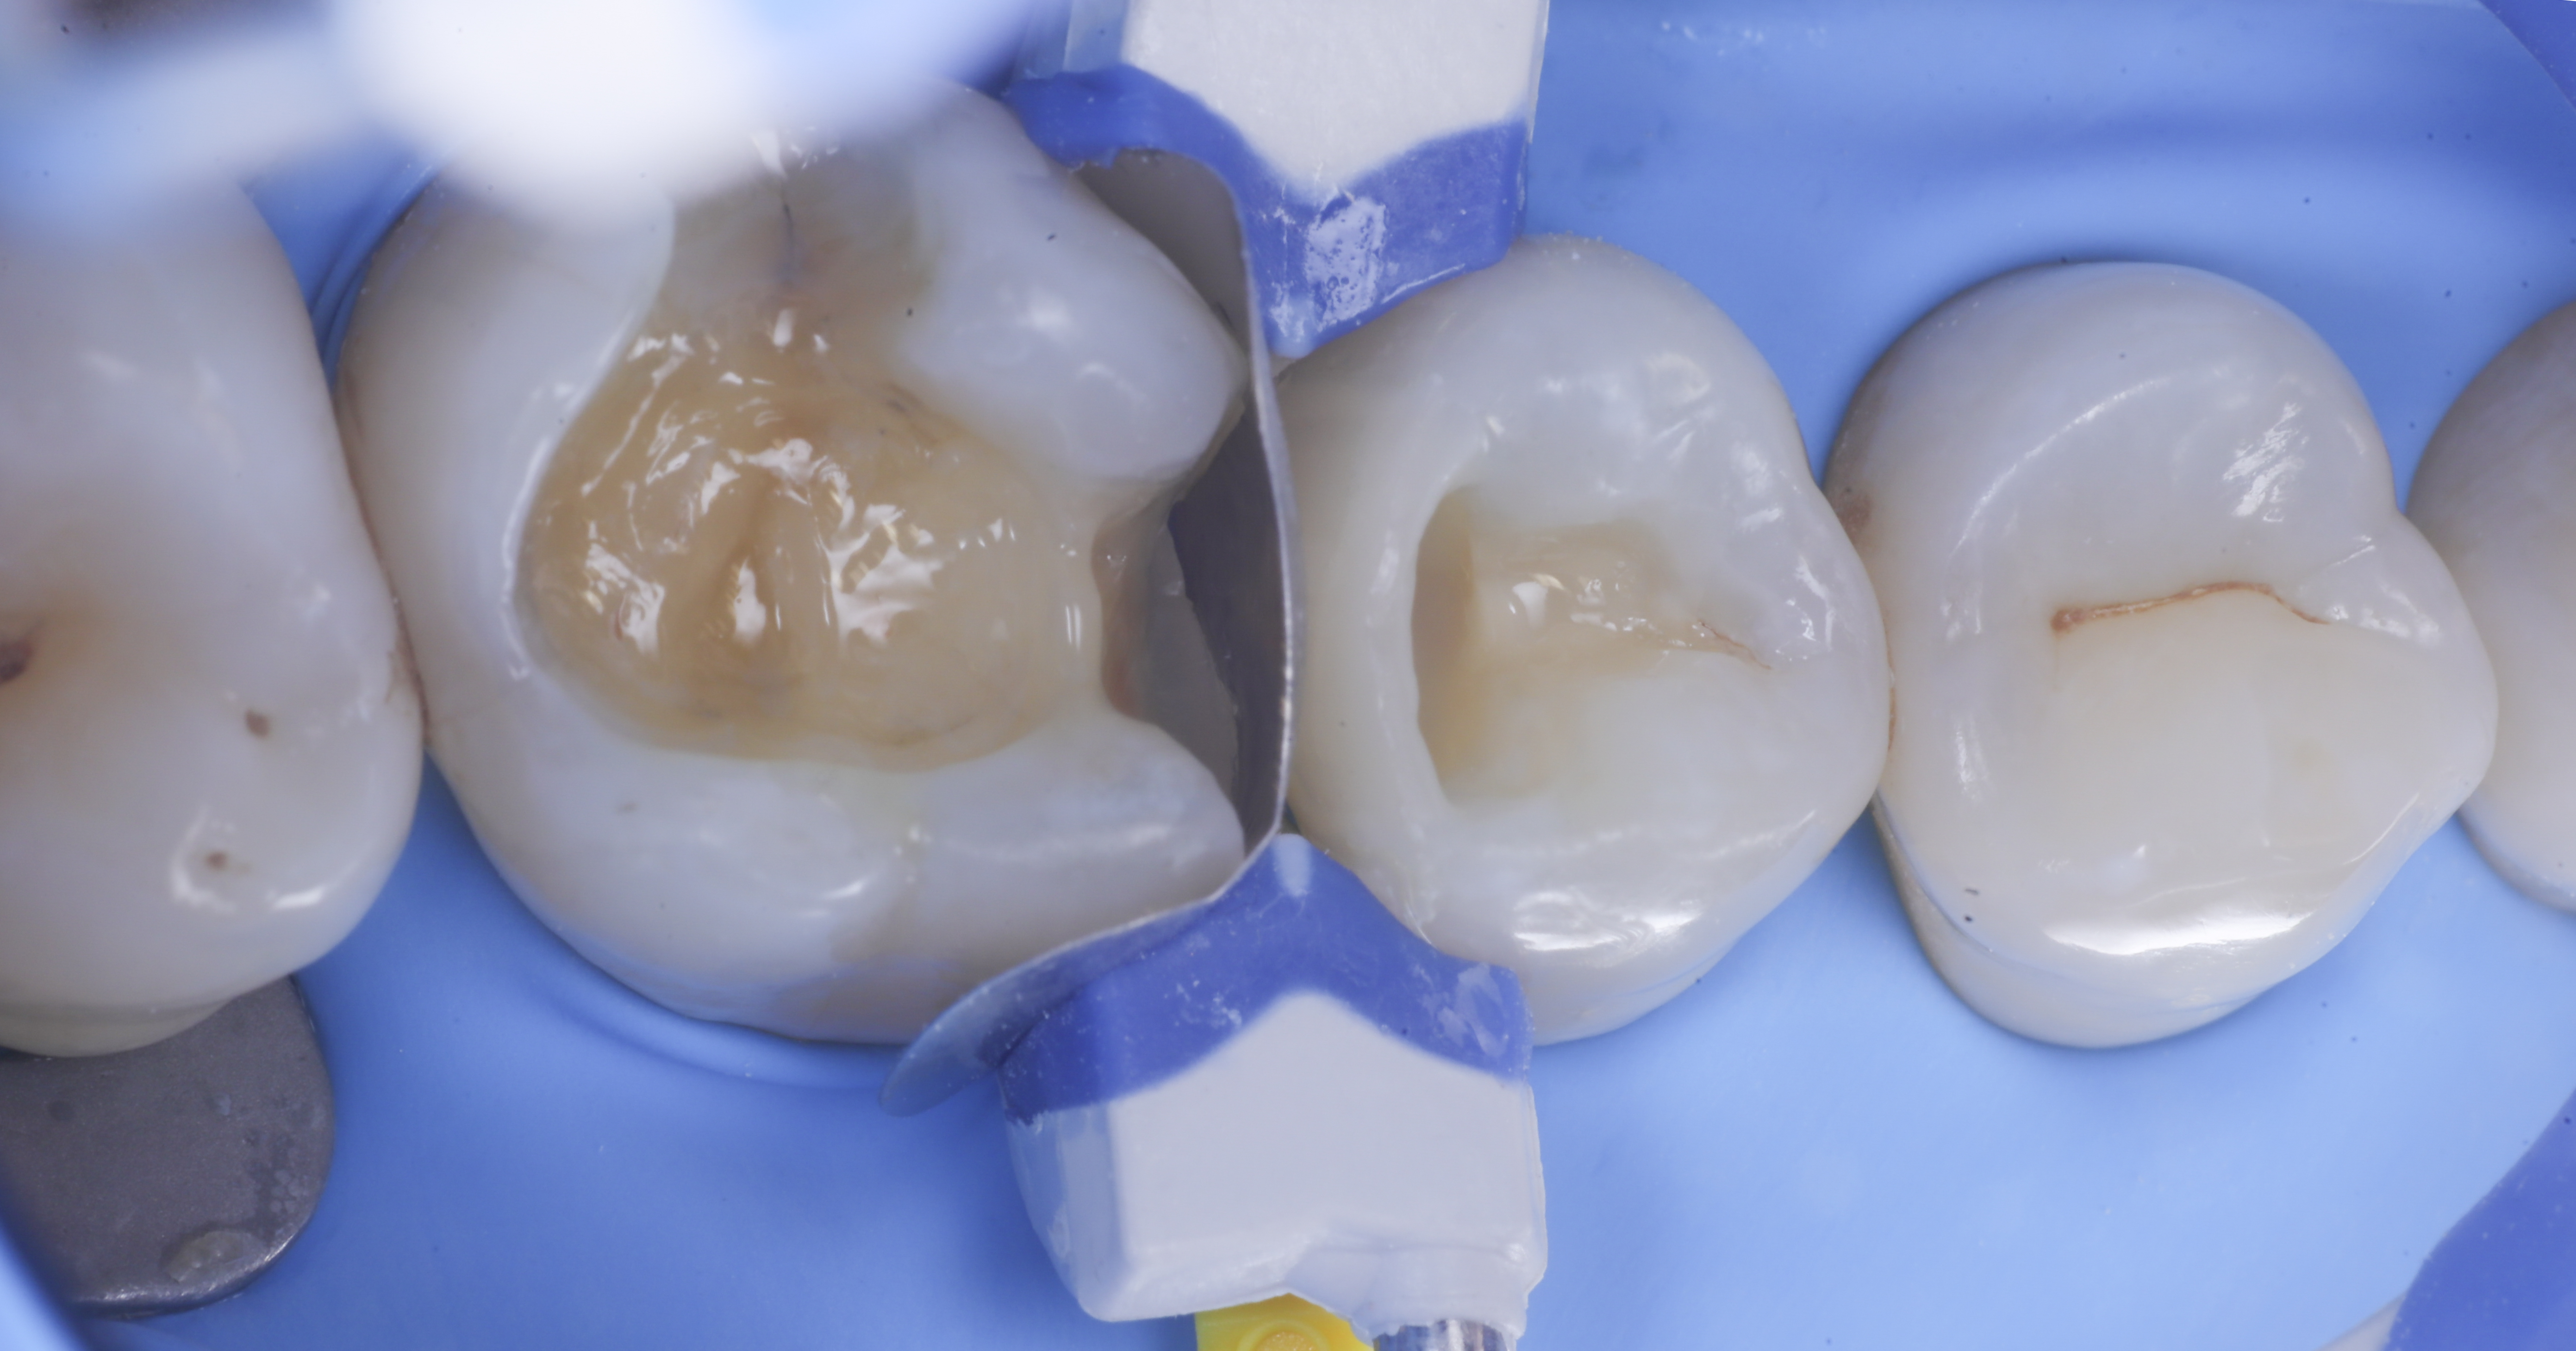

foto 4 Aspetto della chiusura cervicale e sulle pareti assiali dato dalla prima matrice

foto 5 Aspetto della chiusura cervicale e sulle pareti assiali della seconda matrice